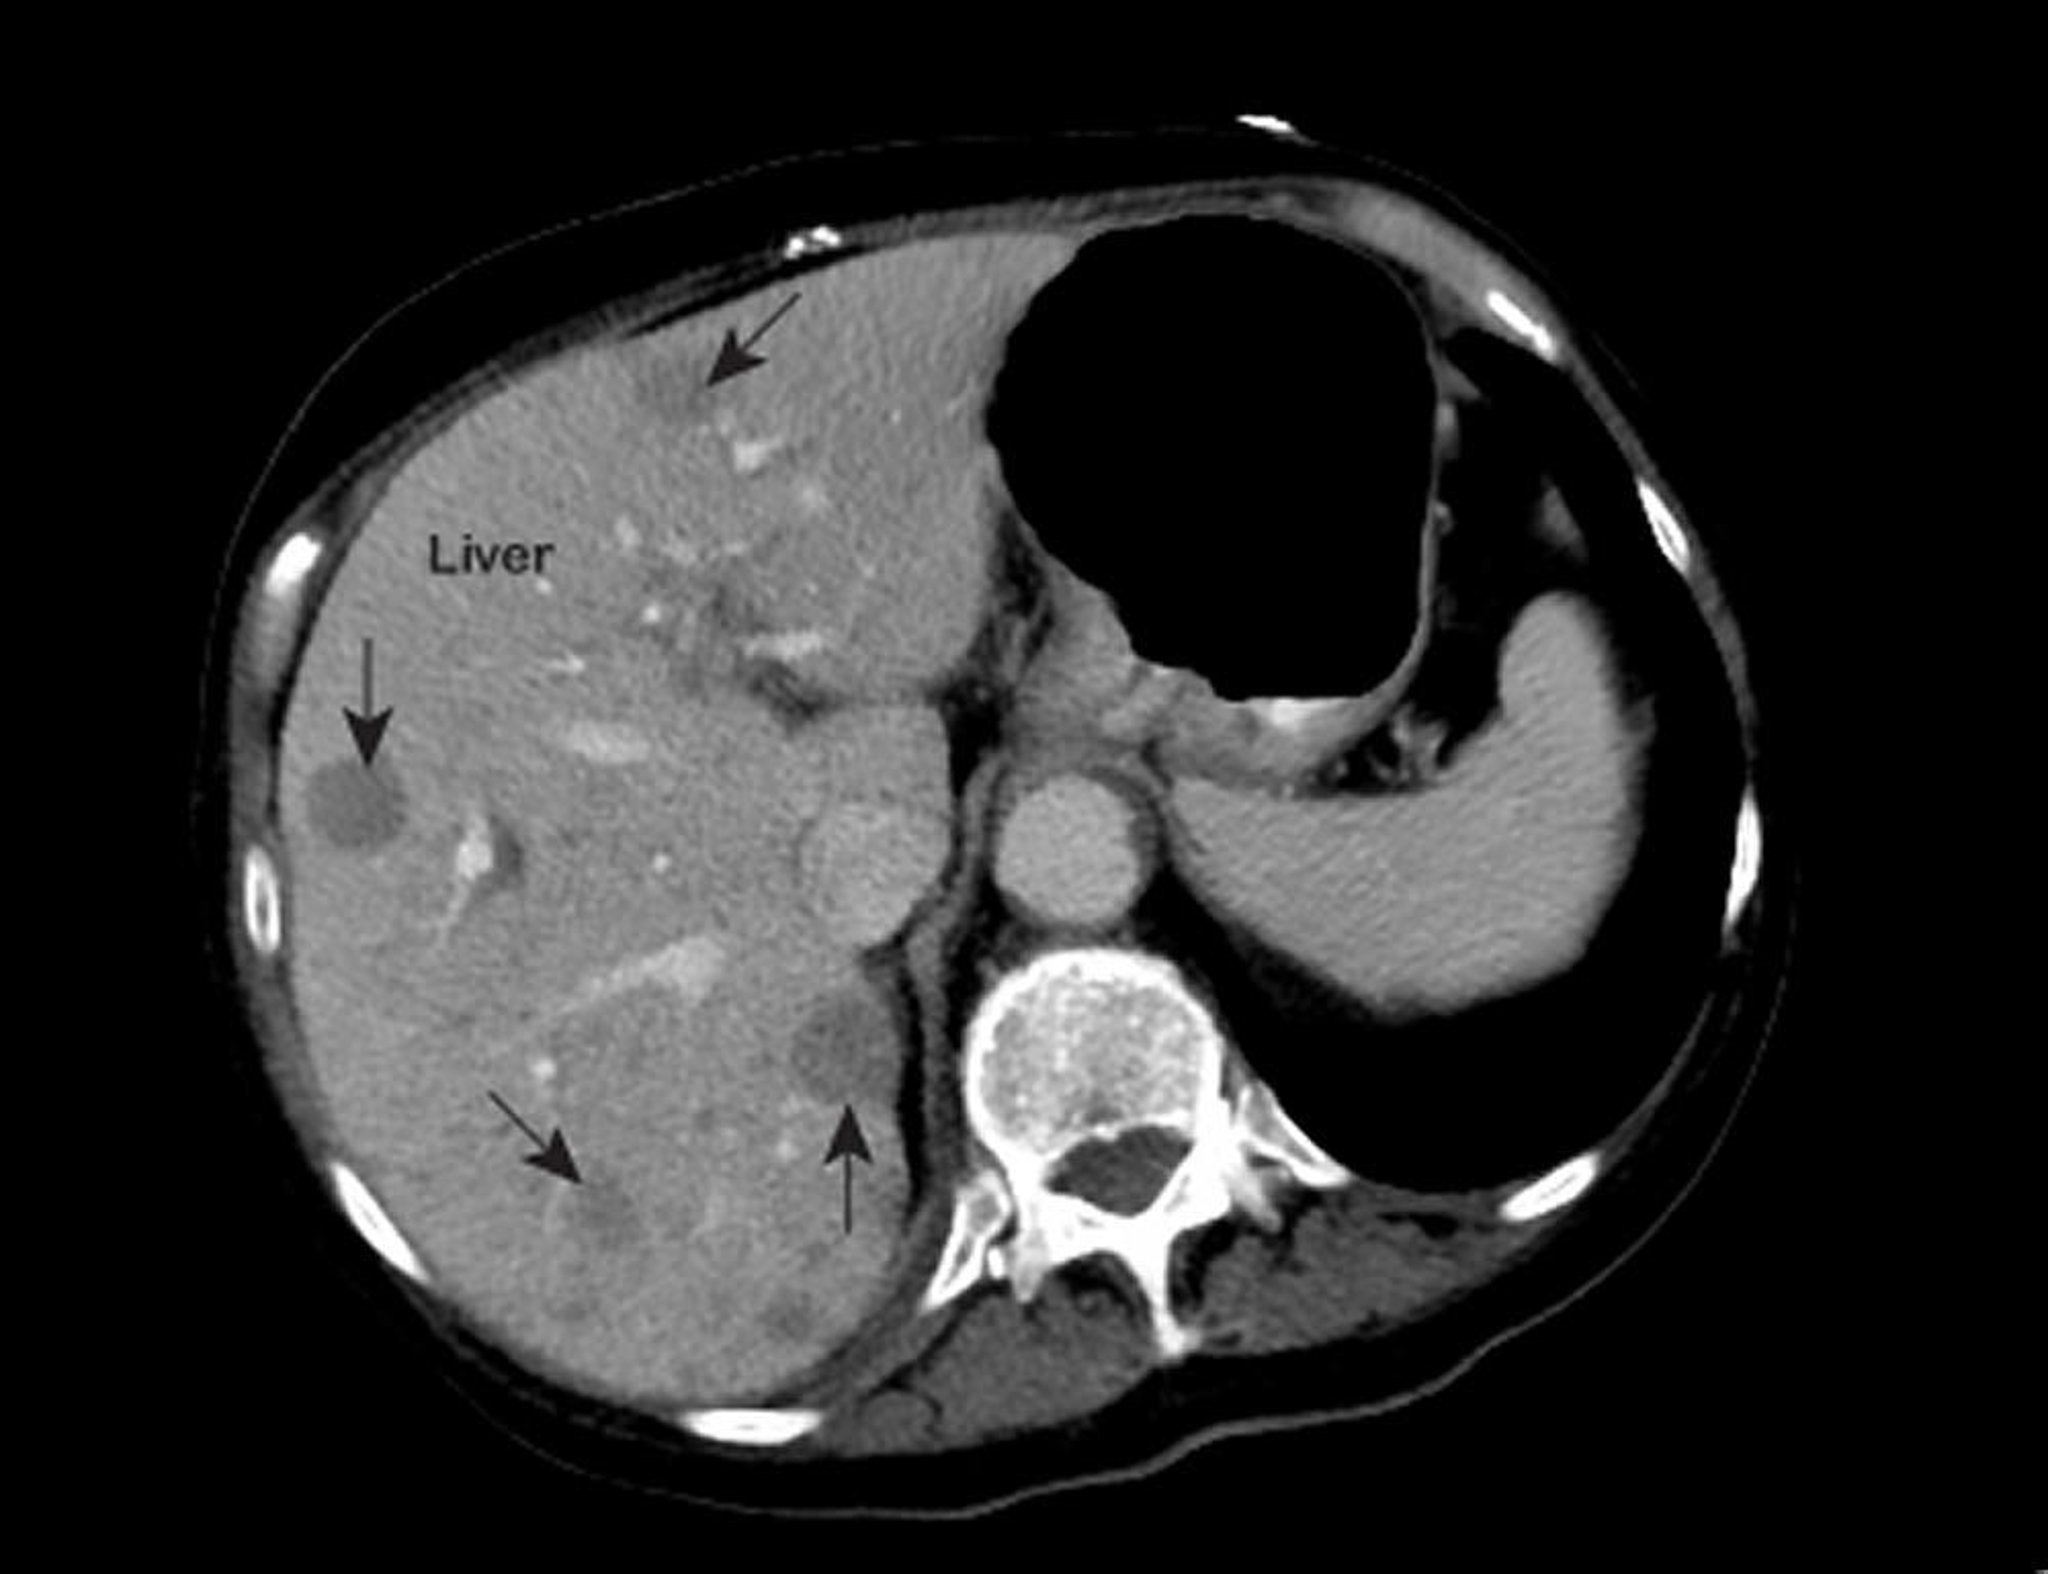

Câncer metastático do fígado

Uma ressonância magnética (RM) anormal do tórax mostra áreas anormais (assinaladas por setas) dentro do fígado. Esses achados são típicos de câncer metastático do fígado.

Foto por cortesia do Dr. Patrick O’Kane.